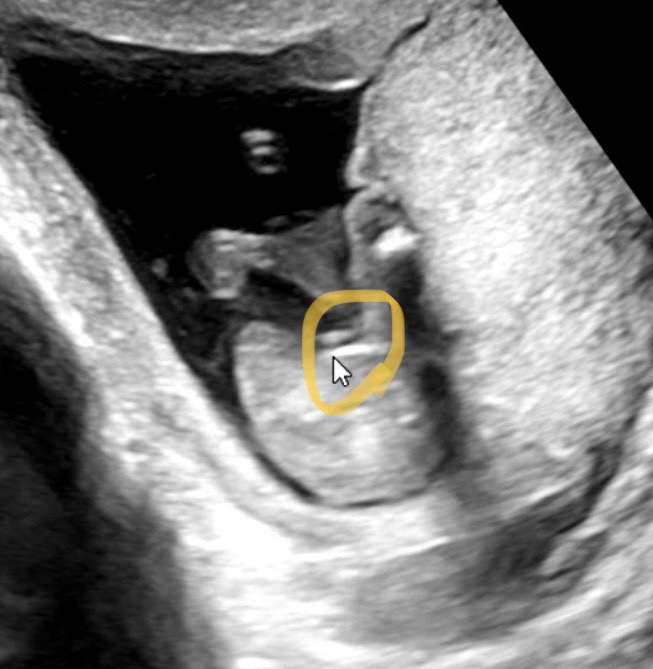

16주 아들맘이네용 초음파 구경하고 가셔용

16주 2일차 2차 기형아검사 다녀왔어용! 다리사이에 뭔가 있는것 같다구 하시네용 ㅋㅋㅋ 초산이라 어떻게 보는지 잘 몰라서 어렵긴 하지만 그래두 의사선생님께서 전문가이시니 믿고 가렵니다! 아들맘 두근.. 출산 전까지 운동 열심히 할거에요..!!